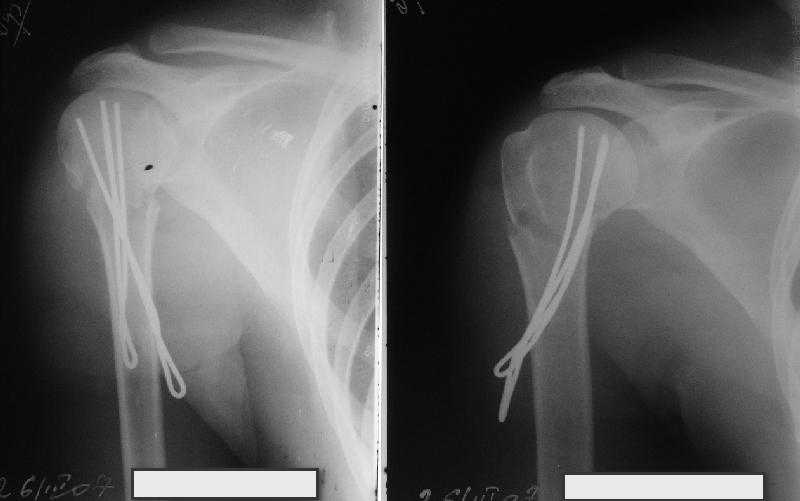

Неправильно выбранная тактика по фиксации или технические ошибки во время операции могут привести к серьезным осложнениям. Здесь привожу

пример из нашей практики, вроде обычный перелом шейки, фиксированный популярным методом "Сиэтла" - множественными спицами 2.8 мм с резьбой на конце.

При первичном осмотре в поликлинике через 3 недели обнаружили миграцию двух спиц, срочно госпитализированному на второй день перед операцией на всякий случай сделали снимок, одна спица находилась под ключицей в шейном отделе (на снимке).